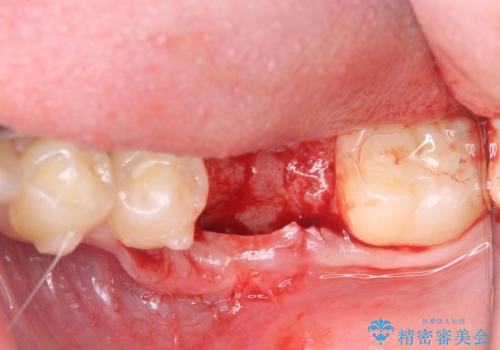

割れてしまった奥歯は抜歯し、矯正治療中の良いタイミングでインプラントを埋入することとしました。

インプラントは、治療期間を短くすることが可能な、ストローマン社のSLActiveを使用することとしました。